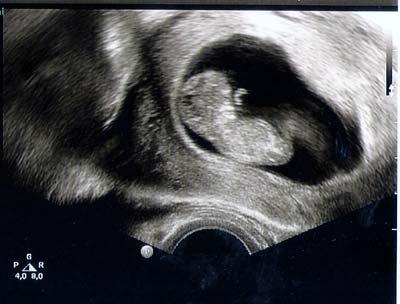

Guten Morgen alle zusammen, ich hoffe es geht Euch gut. Ich komme gerade von meinem Arzt und was soll ich Euch sagen? Es ist alles super in Ordnung alles dran und es ist auch der Zeit dem entsprechend.Es hat uns zu gewunken. Es war so toll. Habe jetzt mein erstes Bildchen. So süß. Mit der Übelkeit wird es auch langsam besser. LG Barney

Hab noch ein Bildchen.

Bild zu

das freut mich, sieht sehr gut aus hab am 5.2. nen termin, denke da wird man hede menge sehen können! lg